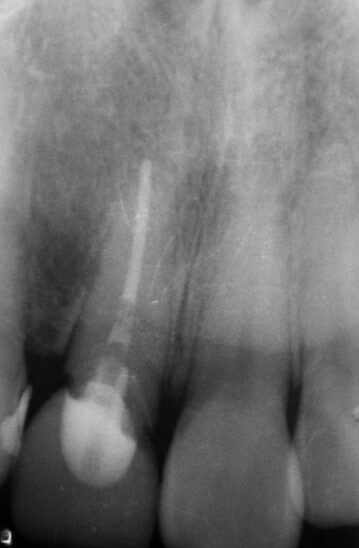

術前 レントゲン

| 主訴 | 前歯の差し歯が折れてしまい、腫れて痛みがある。できるだけ隣の歯を傷つけずに治したい。 |

|---|---|

| 年代・性別 | 30代 男性 |

| 治療部位 | 上顎左側 1 |

| 治療費用 | インプラント手術料 300,000円 |

| 手術回数 | 1回 |

| 治療期間 | 6ヶ月 |

| 手術時間 | 90分 |

| 治療回数 | 4回 |